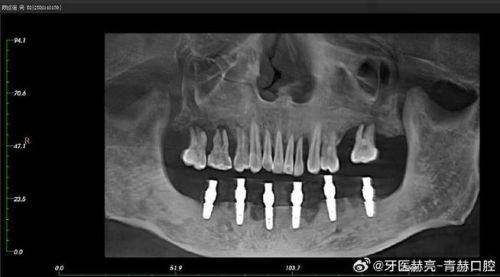

1. 精细种植:现代种植牙技术采用了精良的数字化设备,如口腔CT等,能严谨测量口腔内的骨骼结构和牙齿位置,从而实现精细种植。这不仅提高了种植的成功几率,还能减少对周围组织的损伤。例如,瑞士ITI种植牙在精细种植方面表现出色,能更好地与牙槽骨结合,修复牙齿的功能。